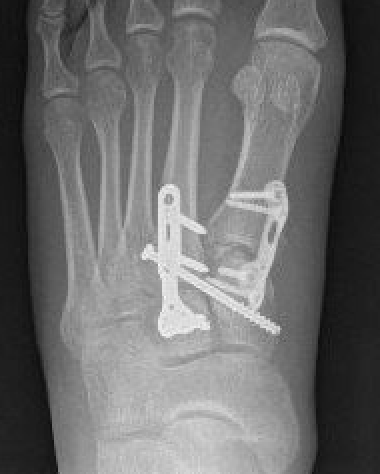

Screw versus bridge plating

- comparison of screw fixation versus bridge plating

- 60 ligamentous Lis Franc

- slightly better outcome scores at 2 years with bridge plate

- anatomic reduction: bridge plate 91%, screw 82%

Bridge plate

Bridge plate to 1st TMT and second TMT with Lisfranc screw